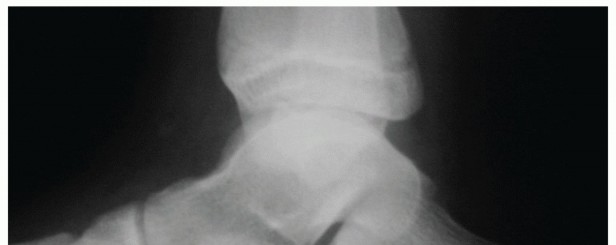

DEFINITION An isolated subtalar arthrodesis can be used in the treatment of a myriad of different hindfoot co…